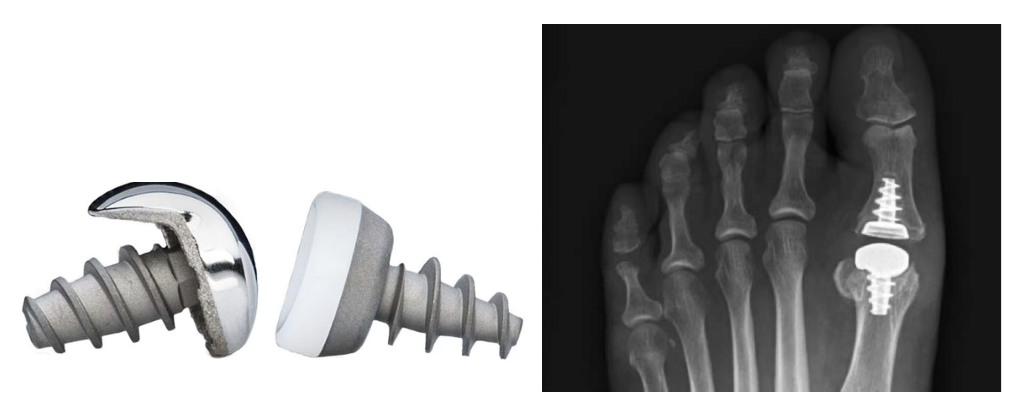

HemiCap / Toe Motion / Grosszehengrundgelenkprothese

Da der erste Mittelfussknochen nicht beliebig verkürzt werden darf, kann nun mit dieser neuen Methode der zerstörte Knorpel des Gelenkköpfchens durch eine anatomisch richtige Halbprothese, bestehend aus einer Verankerungsschraube aus Titan mit aufgesetzter Stahl- "Kappe", ersetzt werden. Bisherige Erfahrungen zeigen eine Verbesserung der Gelenksfunktion um mindestens 60% mit einem Rückgang der Schmerzen meist bis zu deren vollständigem Verschwinden.

HemiCap : komplettes Implantat (li) und im Modell eingebaut (re)

Die neuere Variante, als kompletter Gelenkersatz des Grosszehengrundgelenkes, die Toe Motion Prothese links, rechts das postoperative Röntgenbild.